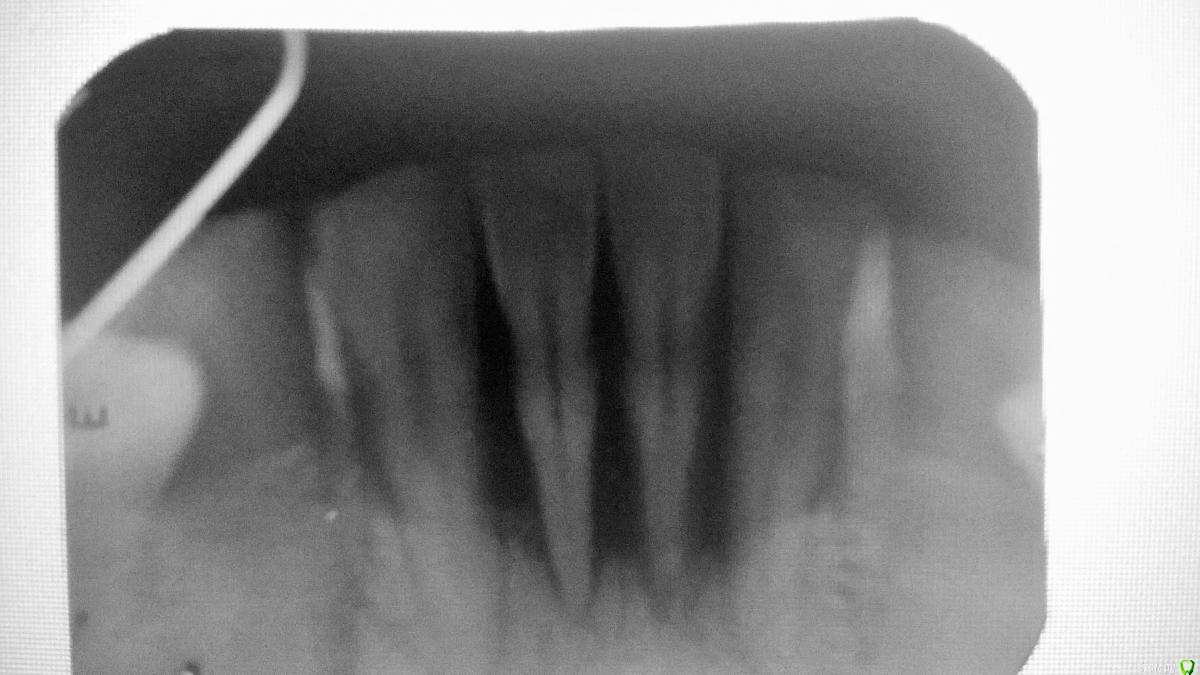

евгния Опубликовано 9 августа, 2015 Поделиться Опубликовано 9 августа, 2015 Здравствуйте ) Уважаемые стоматологи, нужна ваша помощь. Есть вот такая проблема с пердним рядом (видно на снимке прицельном)Предложено два варианта лечения пародонтологом и ортопедом.Пародонтолог(1 вариант ) предложил после депульпирования 31, 41 и кюретажа сделать шинирование 33.32.31.41.42.43. Остальные зубы нижней челюсти залечены, не имеют карманов и убывания костной ткани.Ортопед (2 вариант ) после консультации с хирургом предложили удаление 32.31.41.42 установка имплантов вместо удалённых 32 и 42 , восстановление костной ткани на месте убывшей , но как мне объяснил хирург,это больше косметическая-эстеческая процедура, с последующей установкой 4х коронок.В данный момент депульпированы 31 и 41 ,заложено лекарство и дано время на раздумья(во время депульпирования обнаружилось по два корня в этих зубах и стоматолог проводивший лечение вызвал ортопеда и спросил нужны ли такие затраты (пломбировка каналов,кюретаж, шинирование) для сомнительного восстановления зубов,т.к по их словам 31 и41 через некоторое время будут болтаться в воздухе и вся нагрузка ляжет на соседние зубы)Мои сомнения и вопросы....1 вариант:- целесообразна ли шинирование при таком убывании костной ткани, если да , то сколько она может продержаться при должном уходе . 2 вариант:- меня смущает, что на долгое время будет нарушена дикция , а мне в ближайшие 3-4 месяца это совсем не к стати((- на время приживления имплантов буду носить съёмную пластину с "зубками" , меняет ли такая конструкция дикцию и как сильно ? Ссылка на комментарий